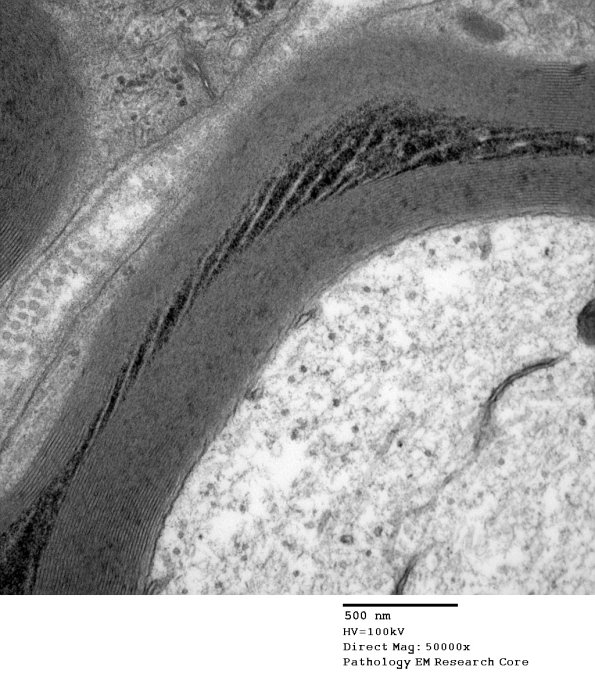

Washington University Experience | PERIPHERAL NEUROPATHY | 3 NORMAL MYELIN & SCHWANN CELLS | 3 Schmidt-Lanterman Clefts | 10C2 SLC (Case 10) EM 163 - Copy

10C2 SLC (Case 10) EM 163 - Copy

Higher magnification of image #10C1. (electron micrograph)